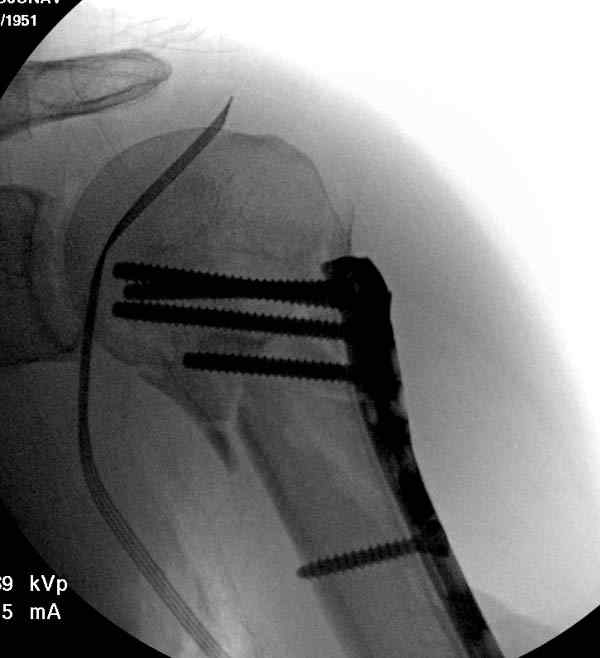

Рентгенограммы действительно с дефектом укладки, но интраоперационная репозиция, можете поверить, была удовлетворительная как в акcиальной, так и в сагиттальной плоскостях. Интраоперационная рентгенограмма прилагается, хотя укладка тоже на ахти. По тактике - разделяю Ваше мнение об отсутствии необходимости реостеосинтеза, а тем более об эндопротезировании, хотя это все было предложено пациентке ведущими ортопедами-травматологами России.

Ошибки встречаются тогда, когда удовлетворяются только одной проекцией рентгена.

Здесь пример открытой репозиции 57 летнего с переломом плеча (1,2) смещение обнаружено на интероперационном снимке. При нормальной прямой проекция (3) угловое смещение обнаружили в аксиальной проекции (4)

После устранения смещения пластина установлена выше (5,6,7) и финальные снимки (8,9,10)